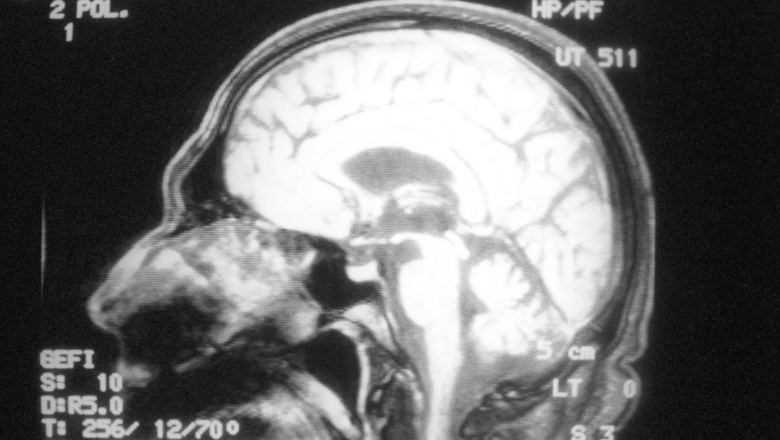

В мозге людей нашли магнитные шарики

В мозге людей нашли магнитные шарики Исследователи из Ланкастерского университета в Великобритании обнаружили микроскопические магнитные частицы в мозге людей. Ученые считают, что они попали в нервные ткани из загрязненного воздуха и могут быть возможной причиной болезни Альцгеймера. Результаты исследования опубликованы в журнале Proceedings of the Далее>>

Ученые доказали, что собаки понимают смысл слов

Ученые доказали, что собаки понимают смысл слов Сенсационное исследование венгерских ученых подтвердило то, о чем давно догадывались многие: собаки понимают смысл слов.В испытаниях приняли участие 11 псов. Все, что им нужно было делать в ходе эксперимента, это спокойно лежать в томографе и слушать голос тренера. Расшифровав сигналы мозга животных, нейрофизиологи пришли к выводу... Далее>>